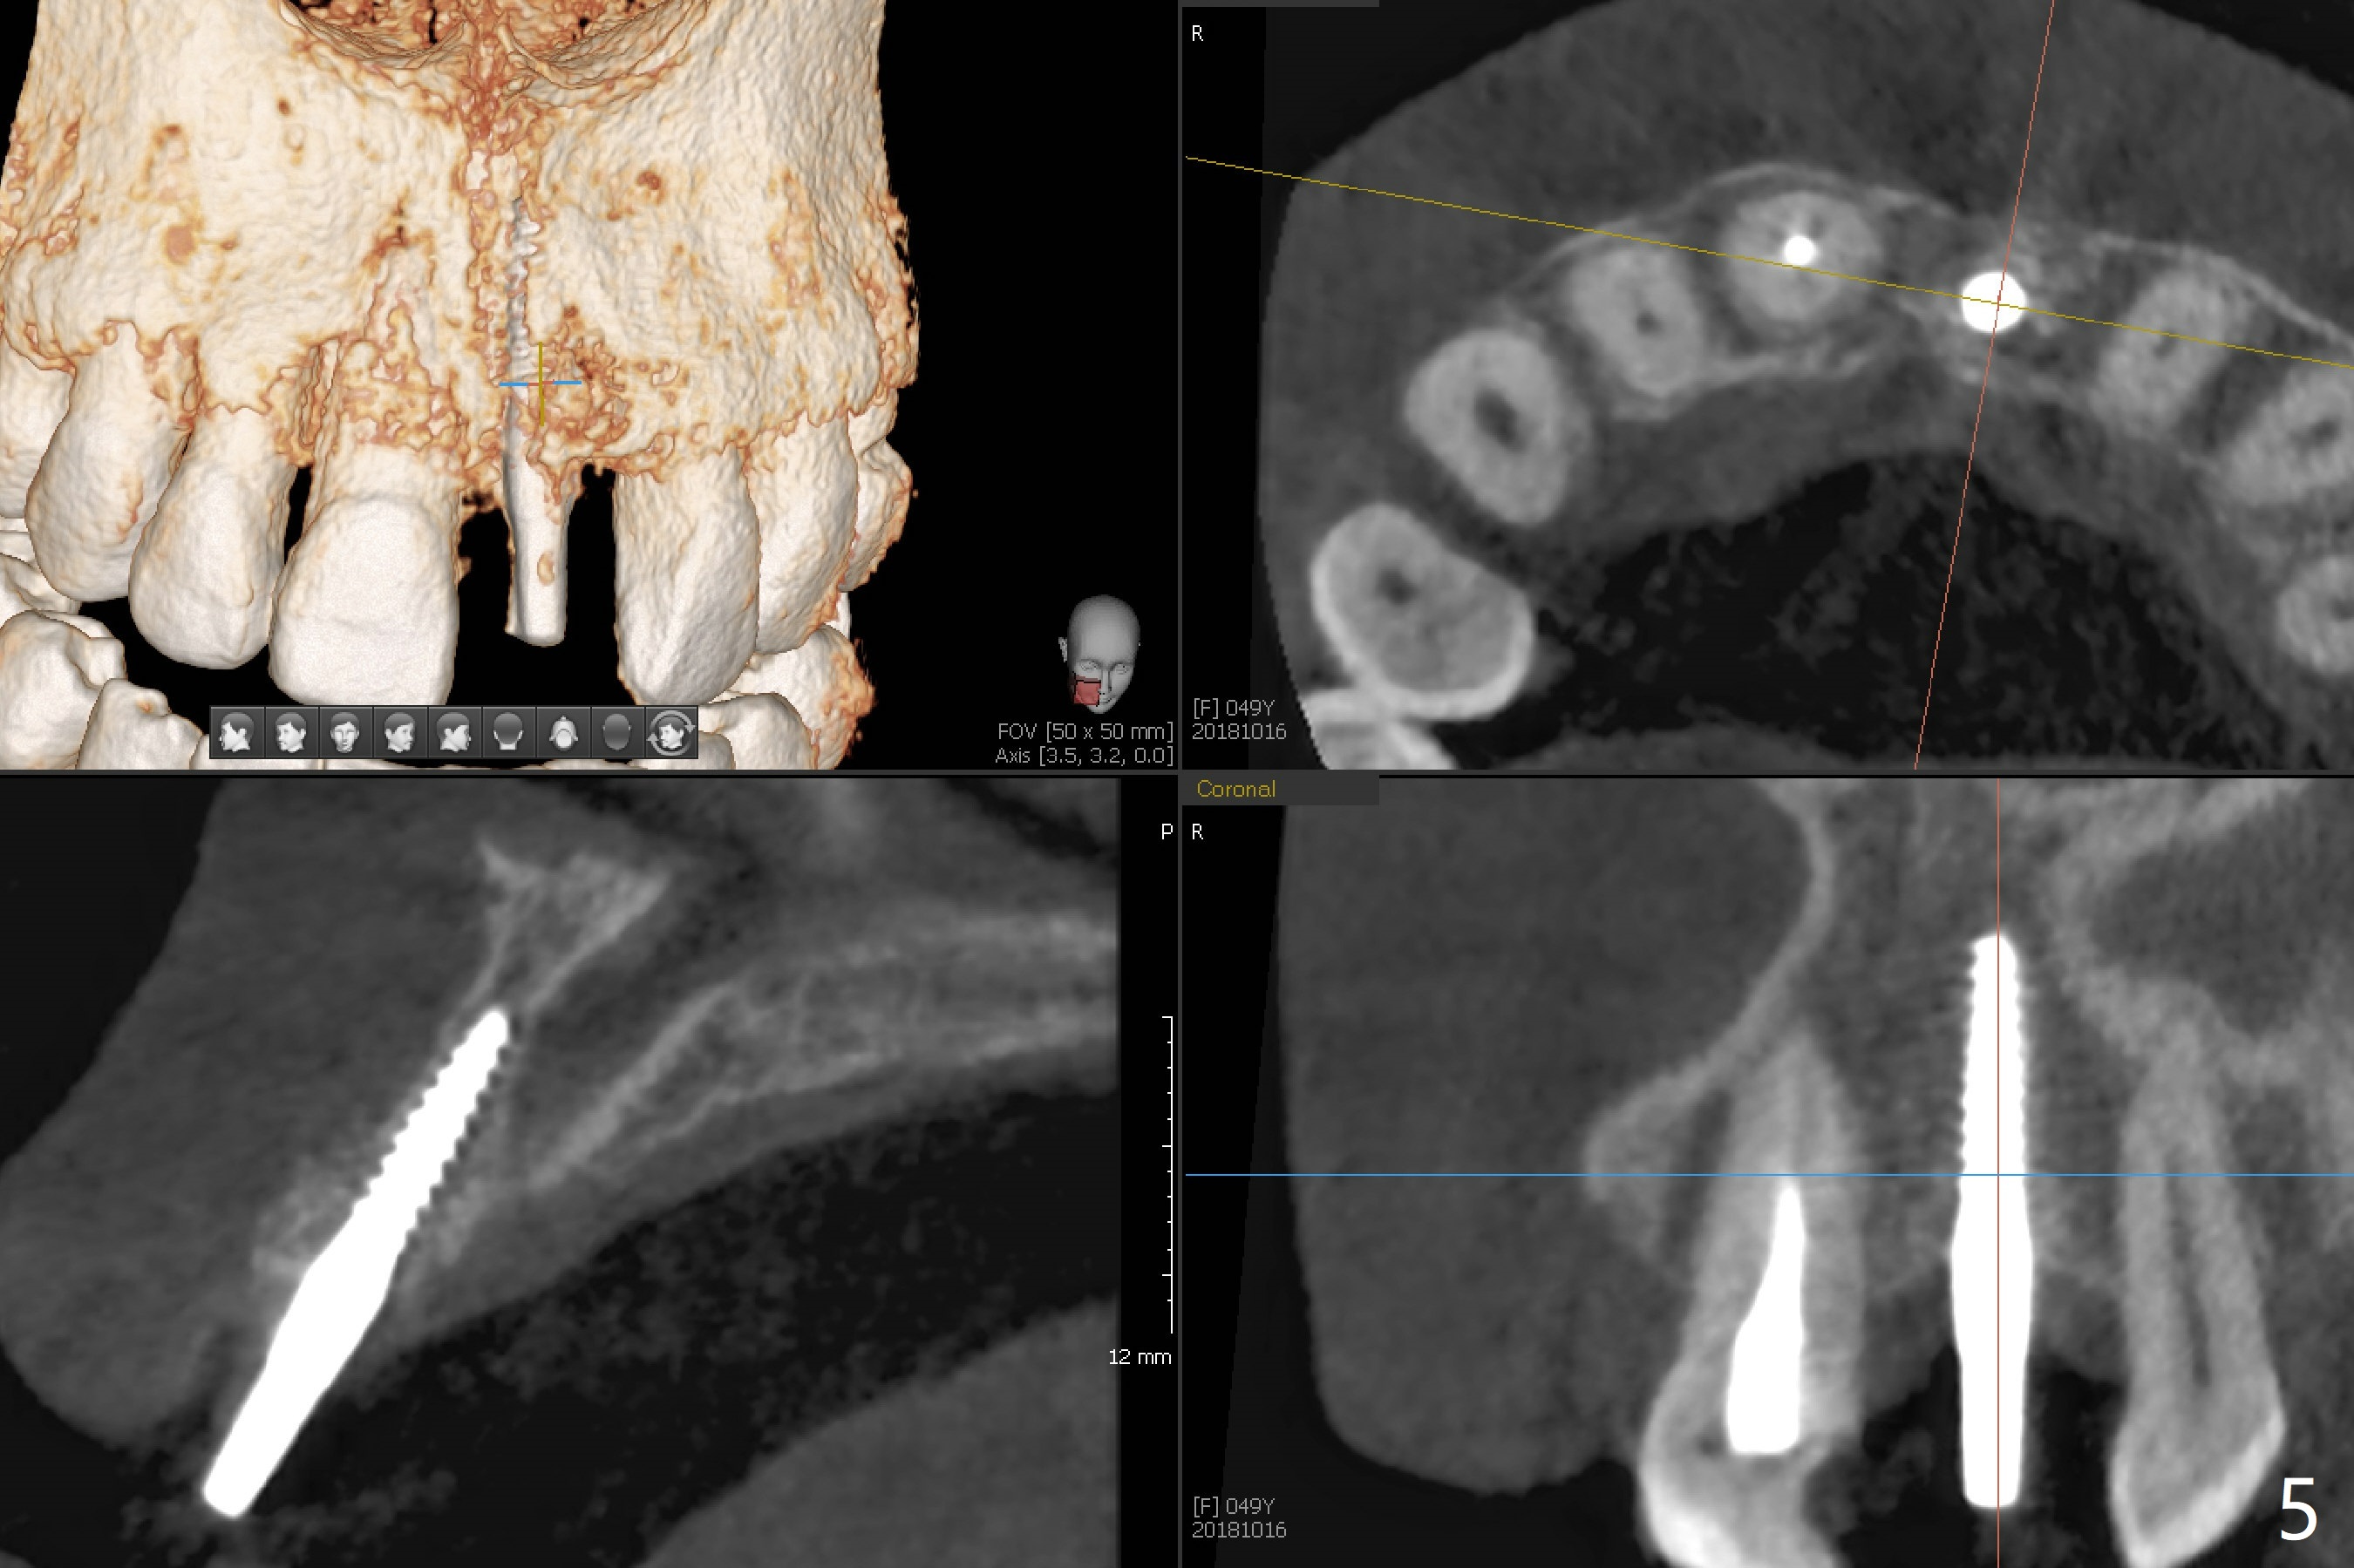

Except the depth, a 2.5x10 mm mini implant is placed with precision (in trajectory) at #9 (Fig.1-5). Confidence using surgical guide for the narrow ridge is enhanced due to placement of two digits against the buccal and palatal plates for tactile sensation. The depth issue is related to overprep with 2.2 mm drills. The torque is <15 Ncm. The immediate provisional is bonded to the neighboring teeth for retention. It appears that smaller drills should be made for guided surgery (such as 1.5 and 2.0 mm). The immediate provisional looks acceptable buccal and occlusal 3 weeks postop (Fig.6,7), although the palatal gingiva is erythematous (Fig.8, which is common after use of drill for access (tissue laceration), OHI offered). Three months postop (Fig.9), the palatal gingiva looks healthy (data not shown), while there is no bone loss around the implant (Fig.10). It remains the same 5 months postop (immediately post cementation, Fig.11) and 3,11 months post cementation (Fig.12,13). The labial gingiva is healthy (Fig.14), while the palatal one is less erythematous and edematous (Fig.15) than earlier (Fig.8).